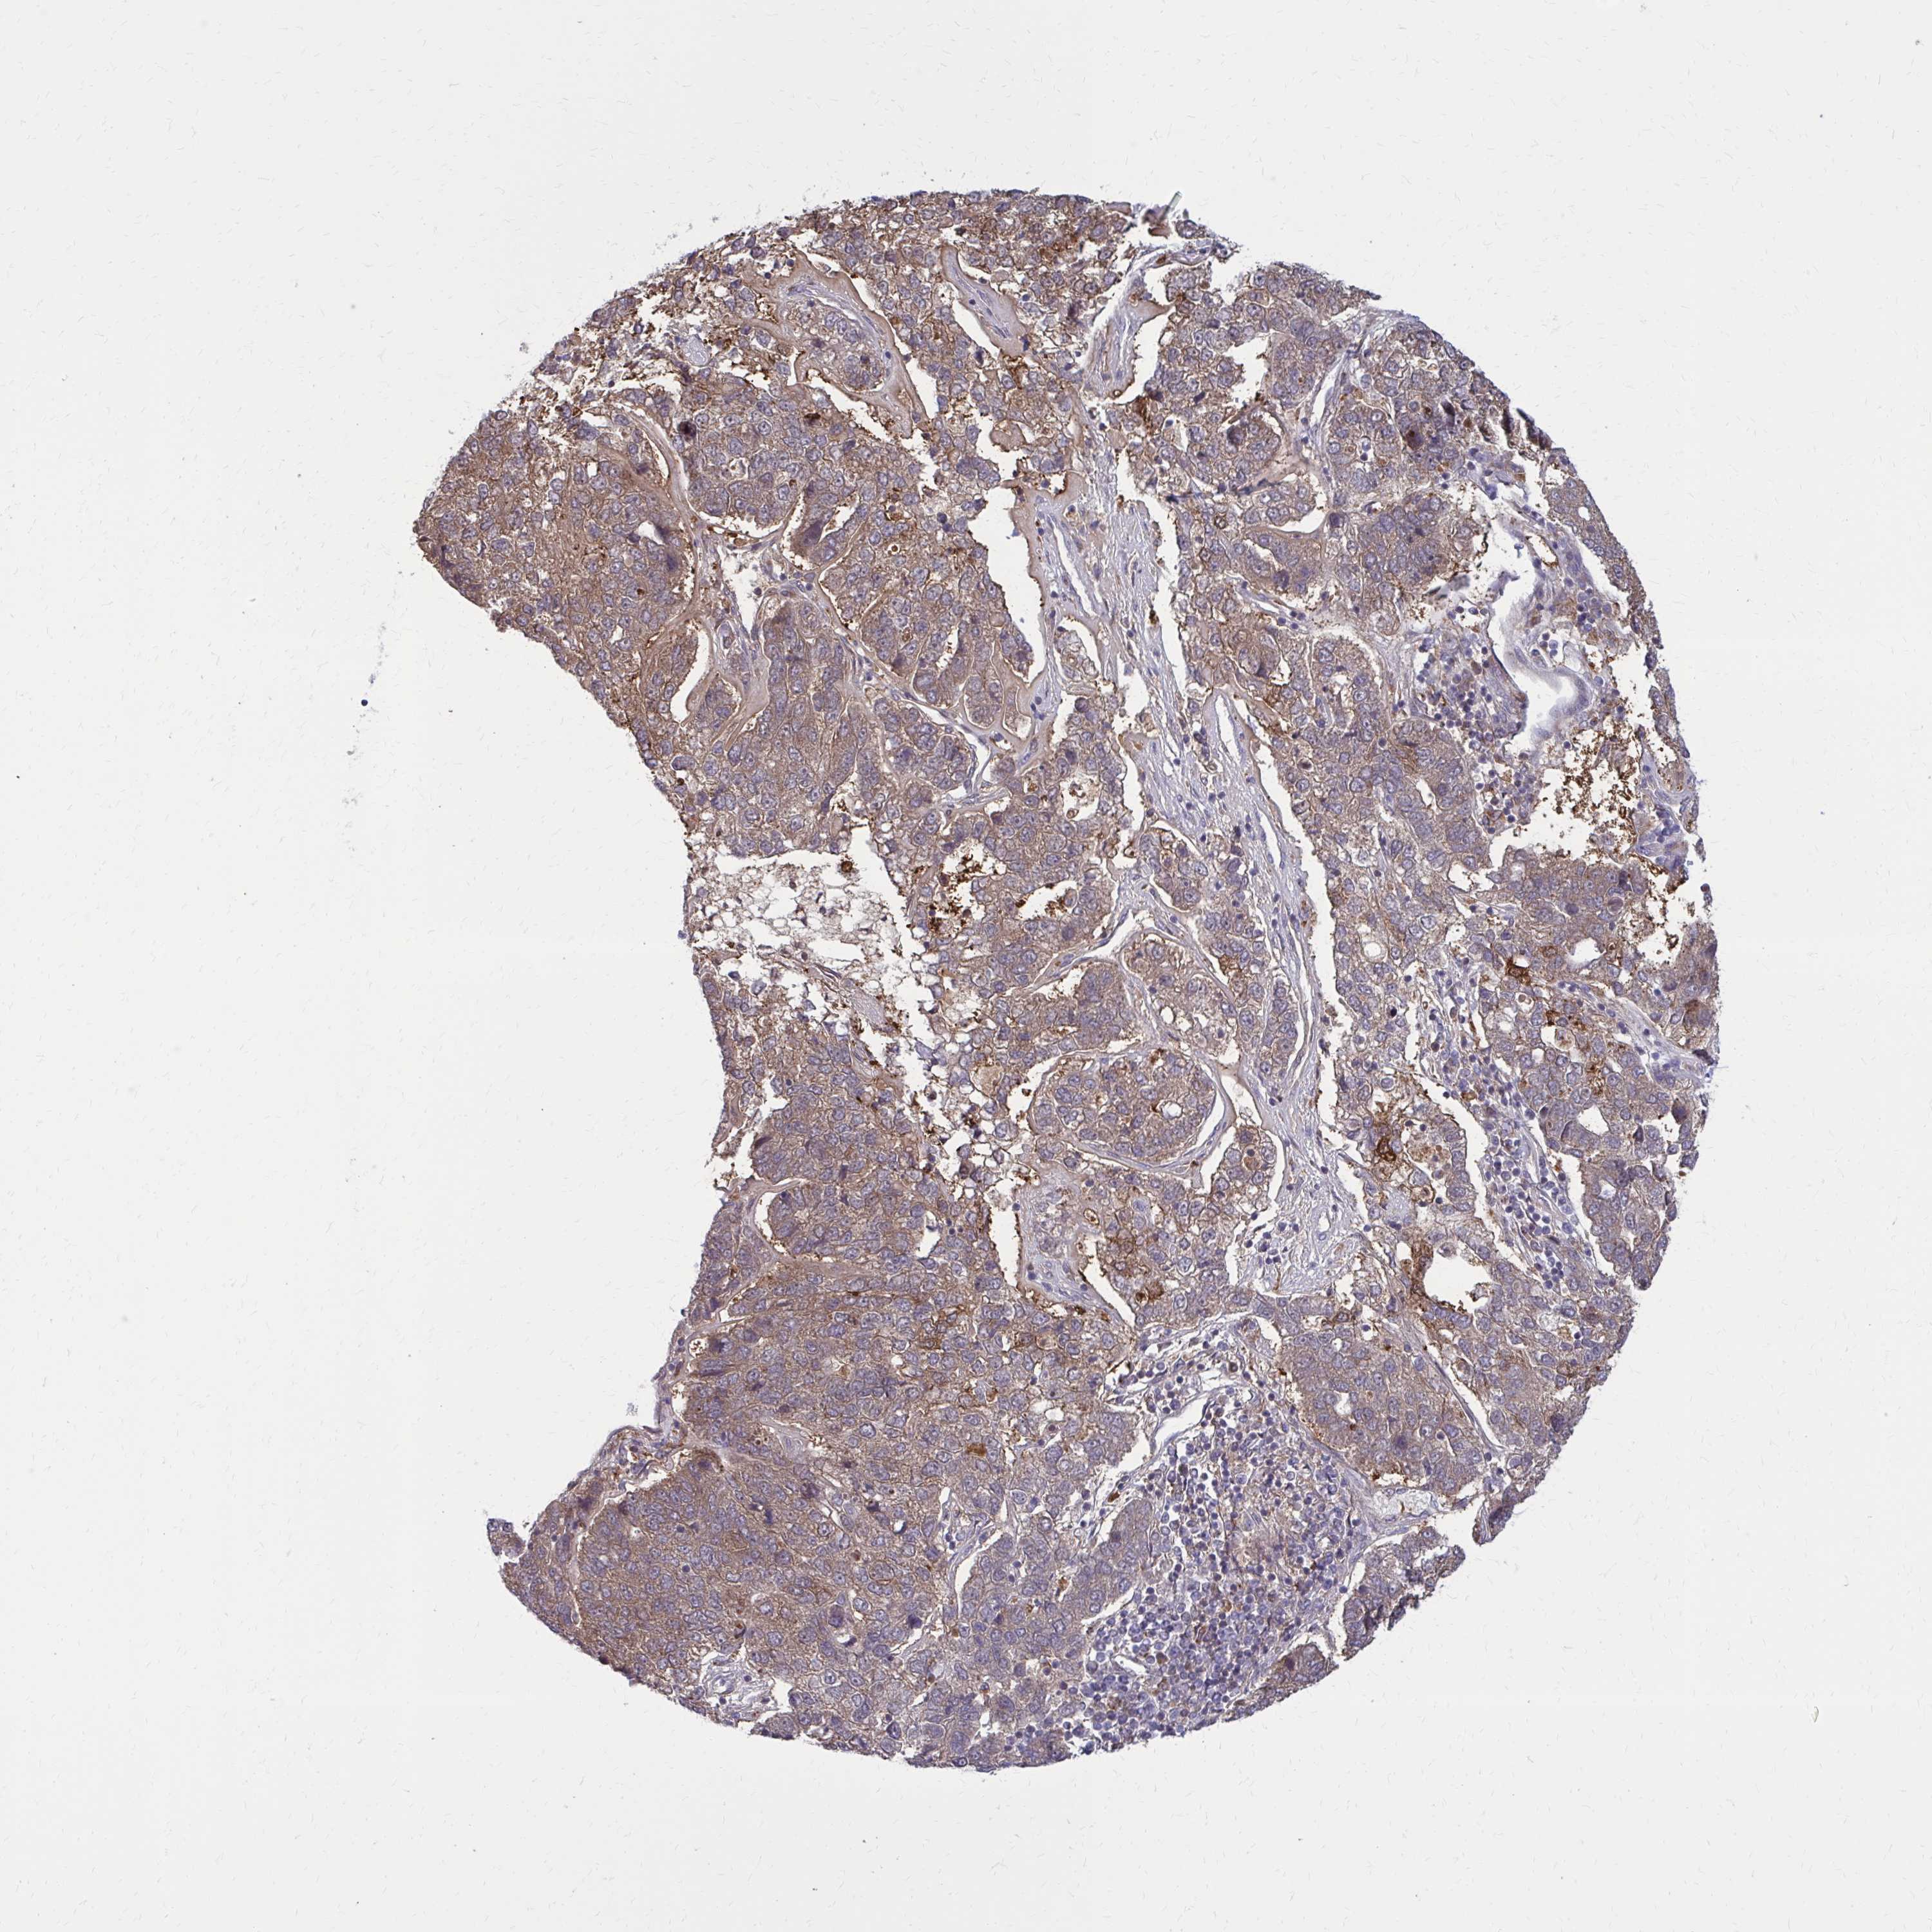

PANCREATIC CANCER - Protein expressioni

A mouse-over function shows sample information and annotation data. Click on an image to view it in a full screen mode. Samples can be filtered based on level of antibody staining by selecting one or several of the following categories: high, medium, low and not detected. The assay and annotation is described here.

Note that samples used for immunohistochemistry by the Human Protein Atlas do not correspond to samples in the TCGA dataset.

Antibody stainingi

Antibody staining in the annotated cell types in the current human tissue is reported as not detected, low, medium, or high, based on conventional immunohistochemistry profiling in selected tissues. This score is based on the combination of the staining intensity and fraction of stained cells.

Each image is clickable and will lead to virtual microscopy that enables deeper exploration of all samples and also displays staining intensity scores, fraction scores and subcellular localization as well as patient and tissue information for each sample.

Antibody HPA051428

Staining

High

Medium

Low

Not detected

Intensity

Strong

Moderate

Weak

Negative

Quantity

>75%

75%-25%

<25%

None

Location

Nuclear

Cytoplasmic/membranous

Cytoplasmic/membranous,nuclear

Adenocarcinoma, NOS